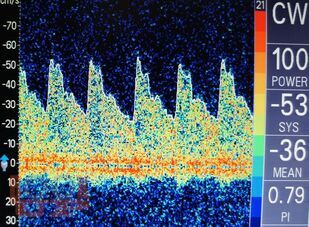

В учебно-методическом пособии для врачей представлена сущность метода транскраниальной допплерографии, основные параметры допплерограммы, применение описанных методик в оценке регуляции мозгового кровообращения. Также дано подробное описание допплерографических паттернов кровотока с их развернутой характеристикой.